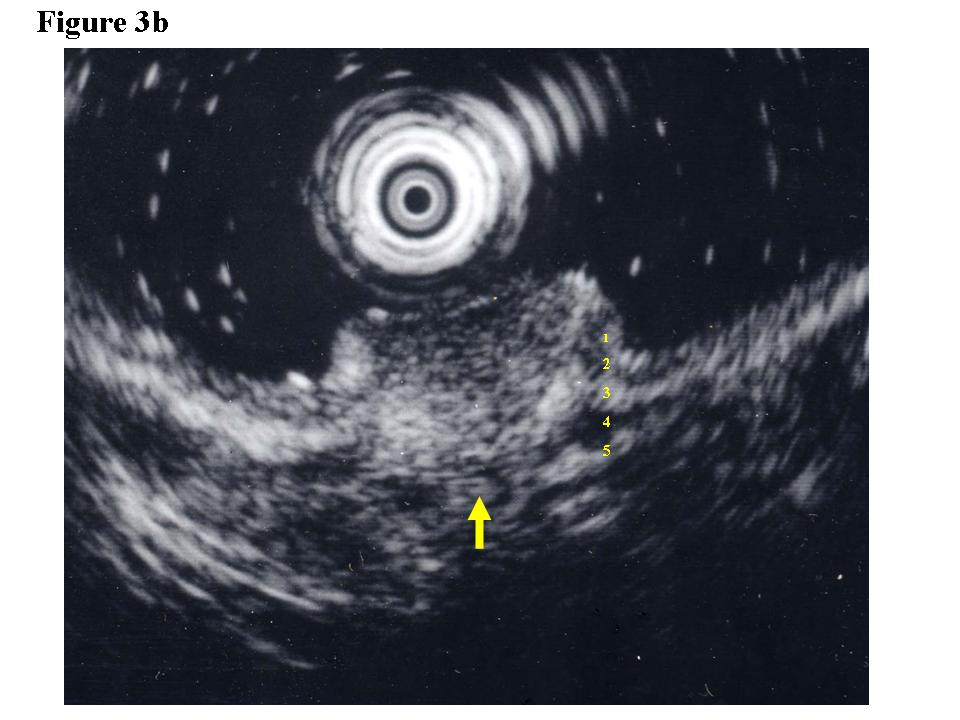

Figure 1.  Early rectal cancer lesion (EUS-M). a) Endoscopic features of superficial depressed type early rectal cancer lesion. b) The tumor was limited to be the first and second layers (EUS-M). c) Macroscopic feature of the tumor specimen.  d) The cancer invasion was limited within mucosa and muscularis mucosae.